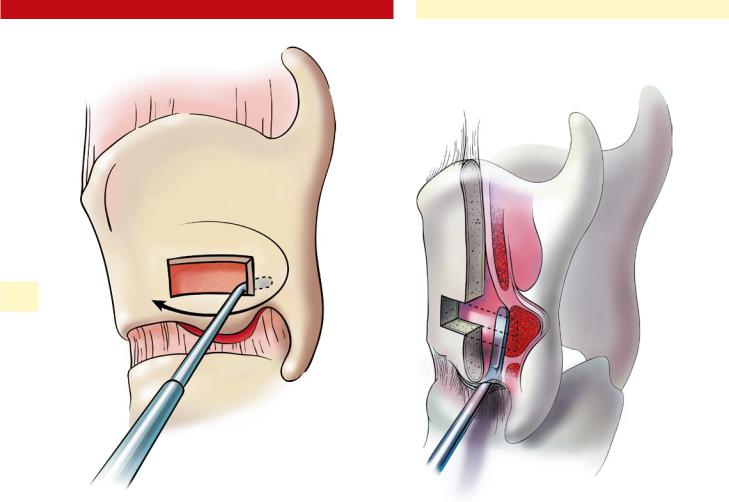

4. MSE + Facepulling *

11. Jaw surgery (Chin wing, BSSO, Bimax..)